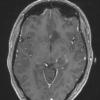

NEOPLASMS (GLIAL)

Astrocytoma, IDH-mutant, WHO Grade 2 (7)